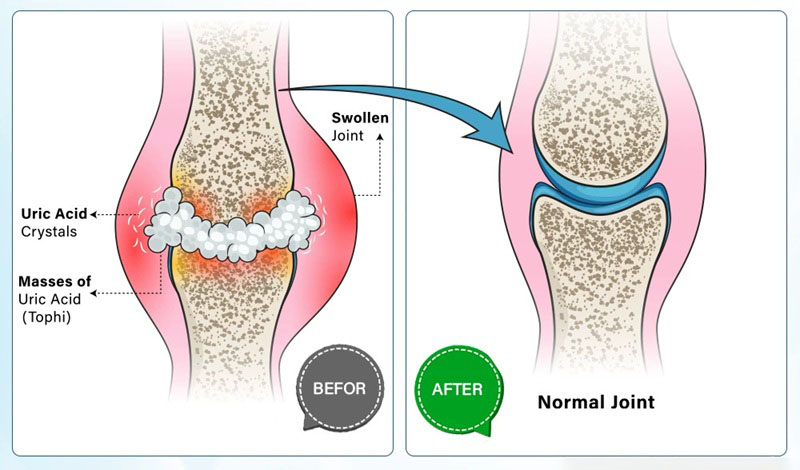

What Are Gout And Pseudogout?

Gout and pseudogout are both forms of arthritis caused by crystal deposition in the joints.

Gout typically affects the big toe (especially the joint at the base of the toe), but it can also affect the knees, ankles, and other joints.

Pseudogout often causes pain in the knees, wrists, elbows, and shoulders. It typically affects larger joints, unlike gout which affects smaller ones like the big toe.

How It Works:

The advanced formula penetrates deeply through the skin, delivering potent agents directly to the source of inflammation.

This targeted approach not only reduces swelling and pain but also accelerates cell repair, promoting faster recovery and restoring comfort to affected areas.